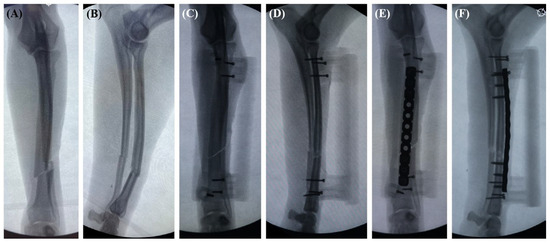

2.4. Surgical Procedure

3. Results